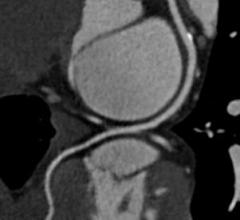

August 15, 2013 — Former President George W. Bush underwent heart surgery on the morning of Aug. 6, 2013, to receive a…